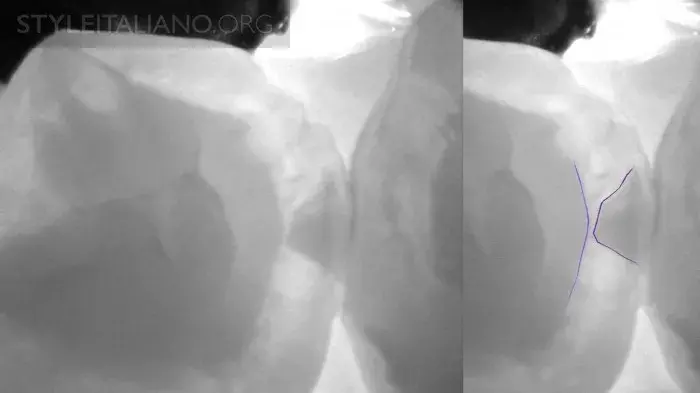

Трещина зуба на снимке

Рис. 30 — Трещина зуба на снимке.

Рис. 31 — Несколько трещин.

Рис. 32 — Вид поражения под трещиной.

Рис. 33 – Несколько трещин вблизи амальгамы.